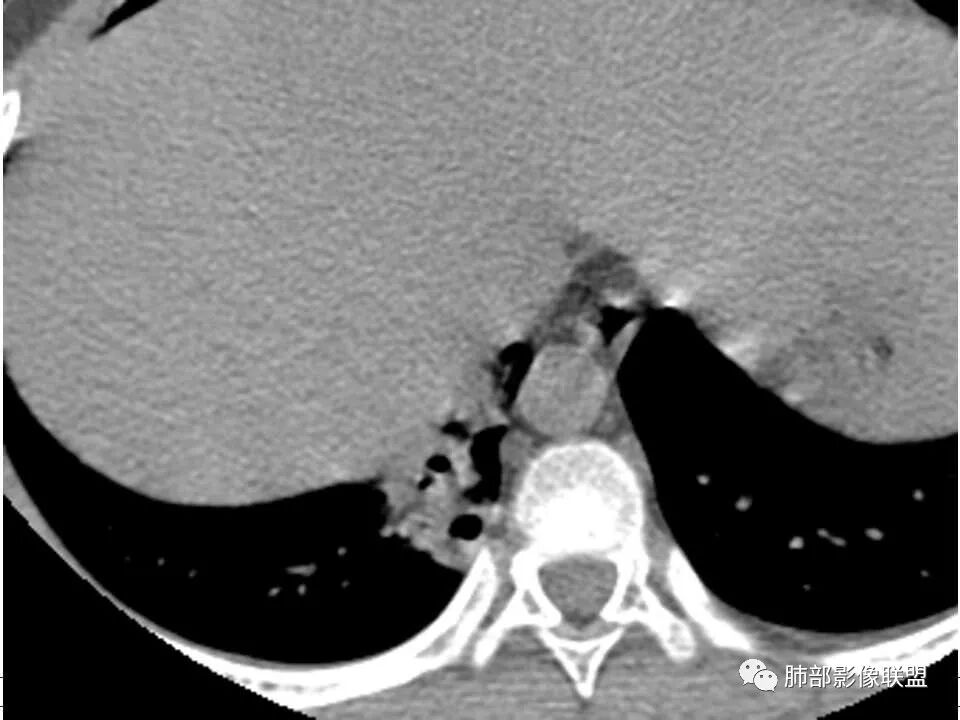

发热,下肢肿胀骨髓水肿,骨髓炎可能;双肺多发结节,部分空洞,左下肺胸膜下楔形阴影,考虑感染性病变,肺梗死;上腔静脉、奇静脉增宽,肝大,考虑股部深静脉拴子进入体循环及肺动脉,综上考虑下肢骨髓炎,深静脉脓毒栓子,肺部感染并肺栓塞

3.资料显示患儿有“股骨及髌骨骨髓水肿及关节积液”表述,结合临床表现及实验室检查,能够符合急性骨髓炎。可惜未能提供骨关节影像学资料。

4.急性骨髓炎多为血源性感染,金葡菌感染居多,好发于血供丰富而流速相对缓慢的干骺端,在儿童因骺软骨阻挡而较少蔓延至骨骺及关节腔(关节腔常有反应性积液),脓腔高张力加之沿哈氏管(Haversian canal)及骨膜下蔓延易于导致骨组织缺血坏死。及时开窗引流有助于防止病情恶化或迁延。